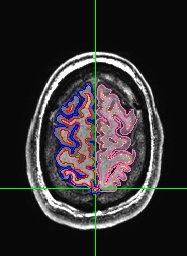

For instance, in this picture, part of the pia-arachnoid-dura has been classified as part of the cortex.

Identify the offending voxels and paint them in black. Here are before and after shots of painting. Note that all voxels in the bad part of the surface most be painted, although only one slice is shown here.